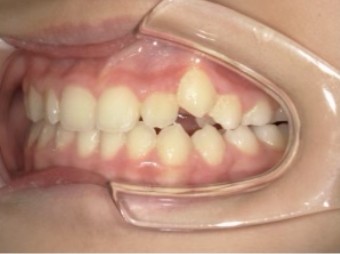

治療中④ 小4:10y1m

左上3が八重歯で萌出中